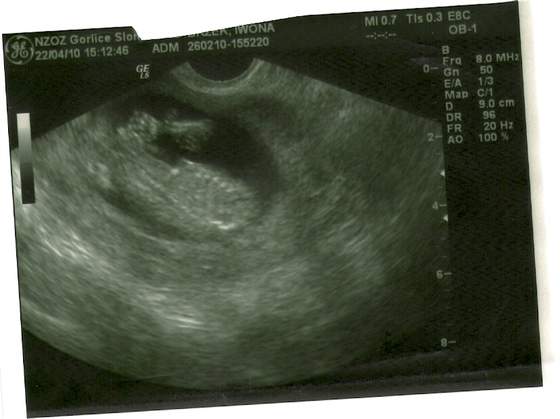

skanowanie0003.jpgskanowanie0004.jpgskanowanie0002.jpga to moja niunia:-)

no i oczywiscie wsio ok jest 2 raczki 2 noznki po 5 paluszkow:) 2 komory mozgowe serducho bije jest zoladek i pecherz moczowy czyli nerki pracuja NT-1.5 KOSC NOSOWA UWIDOCZNIONA:) NO I STRASZNIE LUBI ZAKLADAC NOGE NA NOGE...HMMM